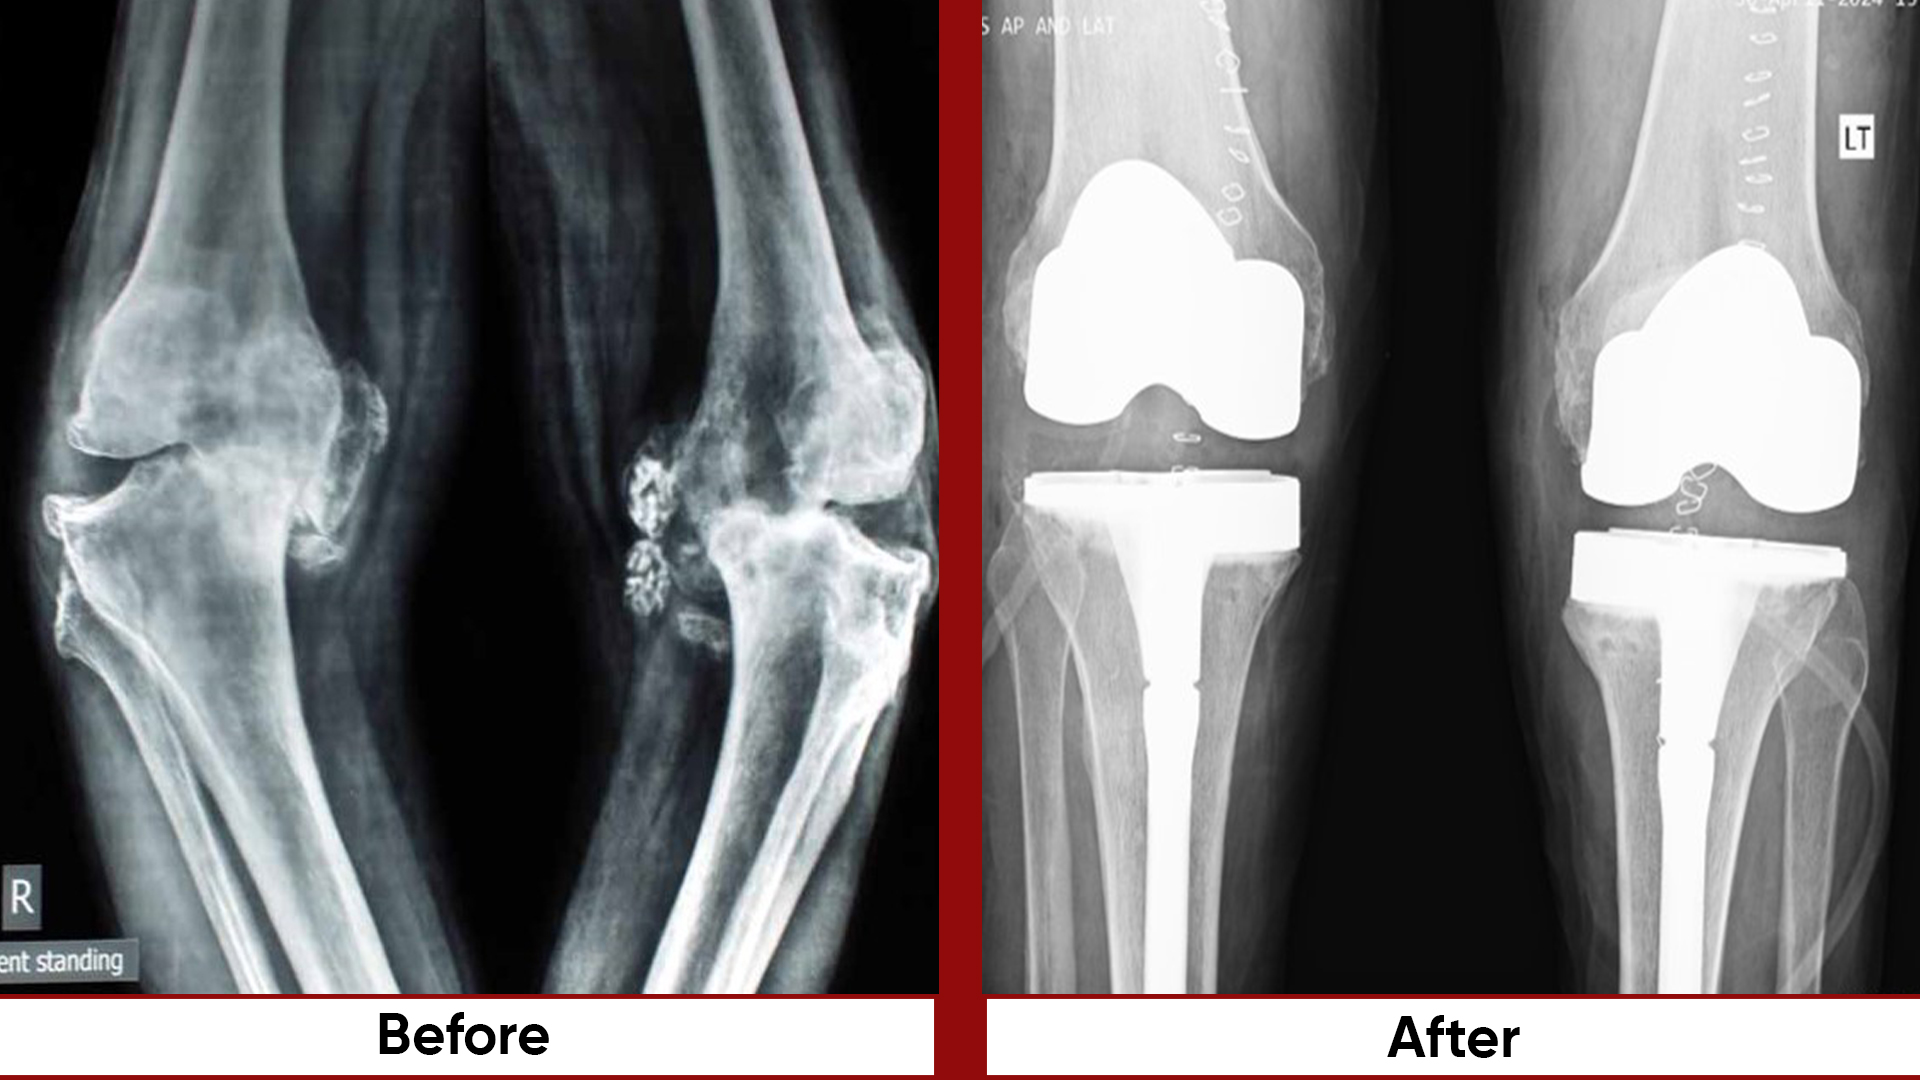

• Total Knee Replacement (TKR)

• Total Hip Replacement (THR)